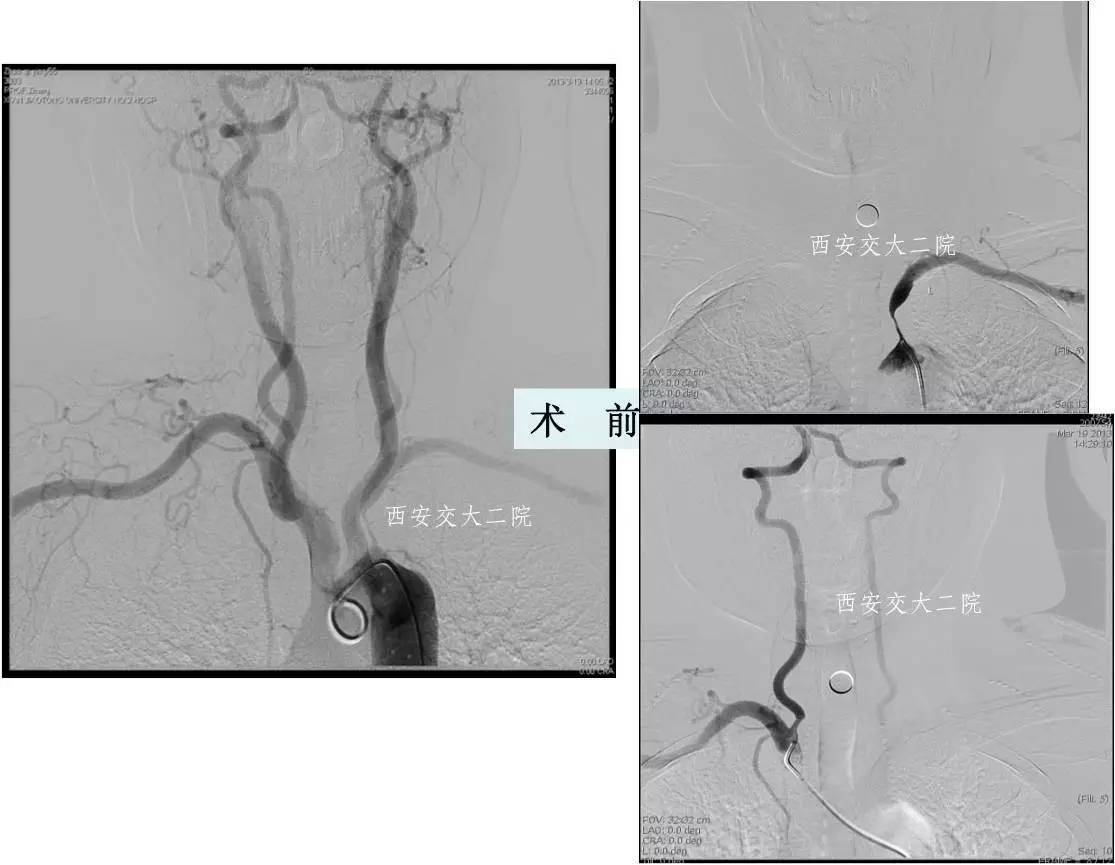

Case 2 右侧锁骨下动脉慢性闭塞再通术

》58岁,男;

》头晕、右上肢乏力4年,活动后明显;

》查体:右上肢皮温低,右侧桡动脉搏动弱,右上肢血压测不到。

Case 3 左锁骨下慢性闭塞再通(2015年)

》男,80岁,活动后头晕7年。

》5年前外院脑DSA发现左侧锁骨下动脉闭塞,右侧椎动脉开口狭窄,给予右侧椎动脉开口支架成形术,术后头晕稍有减轻,但活动后仍头晕,不能跳舞,患者坚决要求治疗。